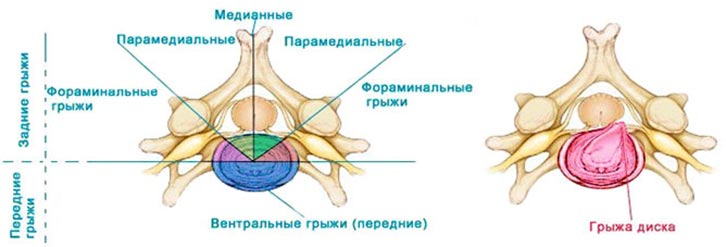

КТ-протрузии дисков: Визуализация и классификация